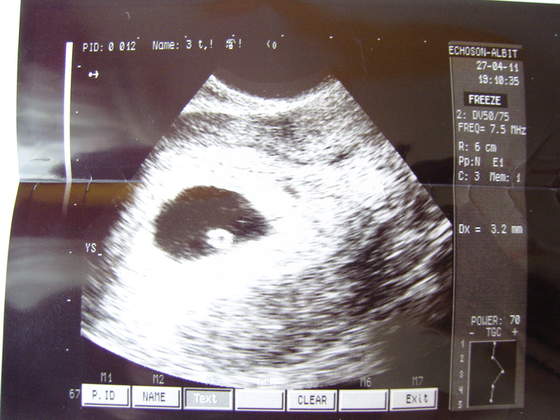

(fotki ze środowej wizyty